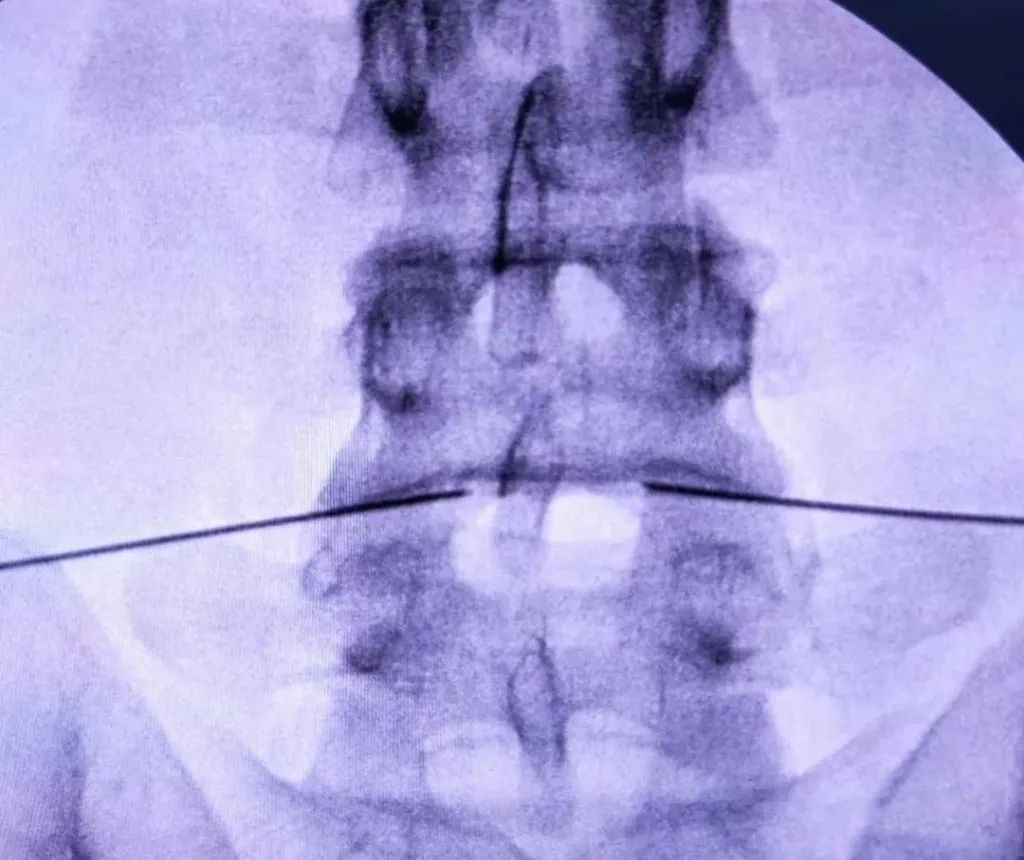

X线引导下L4-5椎间盘双侧射频针置入

正侧位示位置准确

逐渐温控射频消融,射频过程中诱发出患者原疼痛区域,提示位置准确、患者腰部疼痛的原因就是该节段的椎间盘退变

多个靶点射频消融